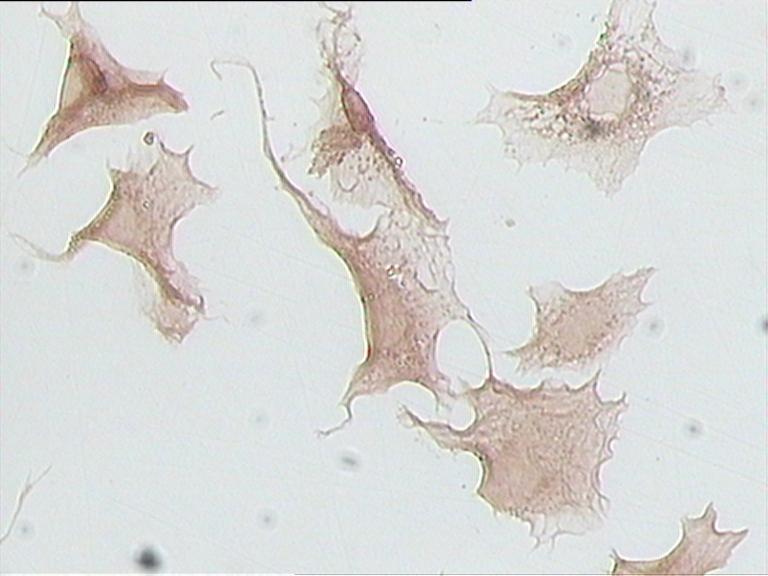

免疫組化【細(xì)胞染色】